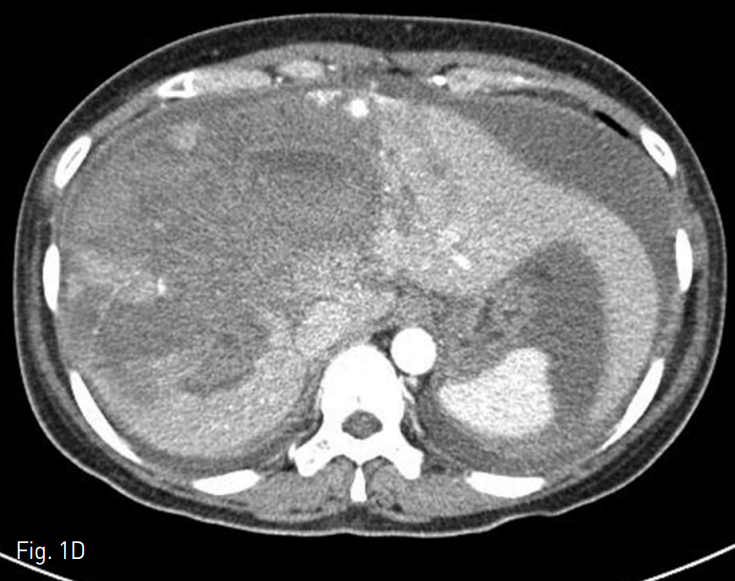

혈관조영술과 색전술을 위하여 우측 총 대퇴동맥을 통해 5 Fr RH catheter를 간동맥에 위치시킨 후 카테터 내에 2.2 Fr 미세도관을 삽입하여 다발성의 점상출혈이 있는 부위에 대하여 gelatin particle을 이용하여 색전술을 시행하였다. 색전술 시행 다음날, 다시 복부팽만과 hemogloin 수치 감소(8.8g/dL → 8.0g/dL)가 발생하여 복부 CT를 시행하였다. 추적 복부 CT상 간 내 혈종의 양이 증가되었고 2, 3번 segment에도 새롭게 다발성의 점상출혈이 보였다 (Fig. 1D). 새로이 보이는 Left lobe의 다발성 점상출혈을 확인하기 위하여 간동맥 혈관조영술을 시행하였으나 명확하게 출혈소견이 보이지 않았기에 간 동맥 외의 다른 동맥을 통한 출혈부위를 찾기 위하여 5 Fr Headhunter angiocatheter를 이용하여 우측 내유동맥의 혈관조영술을 시행하였고 (Fig. 1E, F) 내유동맥 조영술상에서 간 좌분절의 다발성 점상출혈을 확인하고 2.2 Fr 미세도관으로 진입하여 gelatin particle을 이용한 색전술 시행하였다. 이후에 환자는 더 이상의 출혈소견 없이 호전되었다.

F. Subsequent right Internal mammary angiography revealed multifocal active bleding foci at the left hepatic segment of liver. Arterial embolization with gelfoam particle was done. And the general condition of patient was improved (not shown).